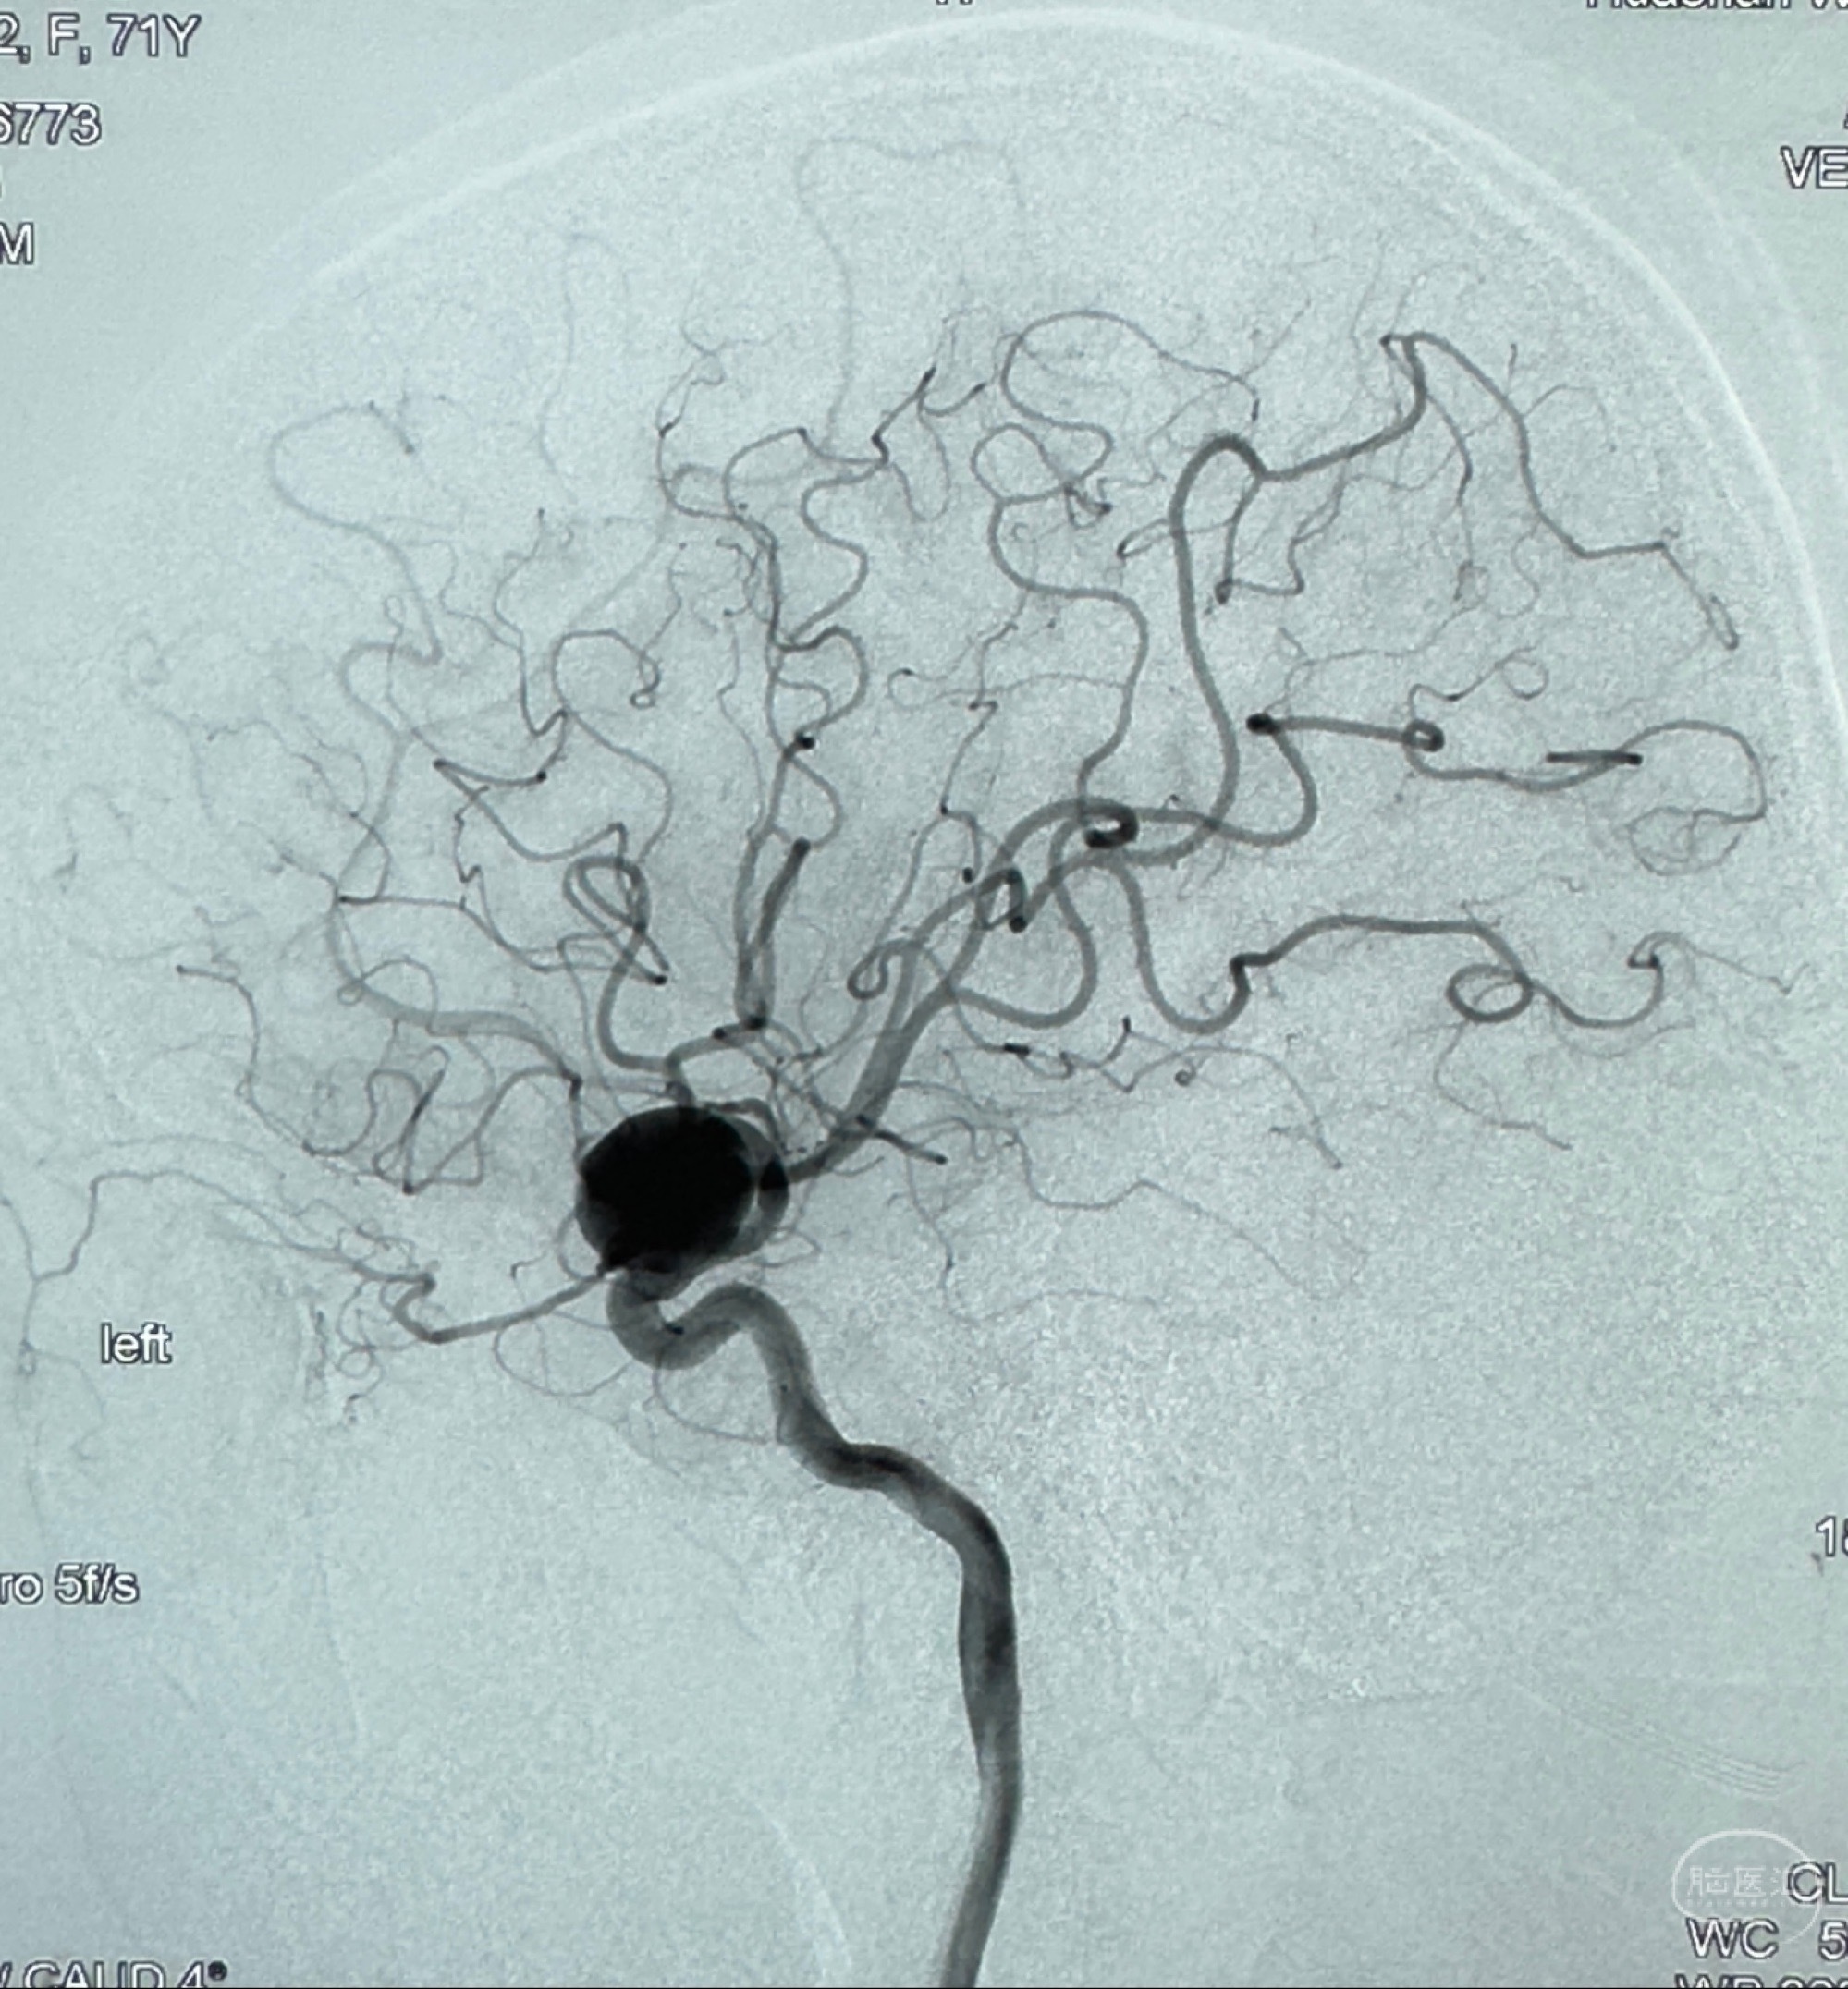

2023-12-27术后第十天复查DSA

支架贴壁佳,但可见射流,咋办?

2024-01-08全麻下再行植入密网支架一枚

Tubridge 4.5-35mm

支架植入顺利,贴壁佳,支架内血流通畅,动脉瘤内血液滞留明显